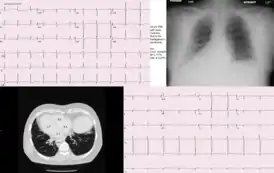

![]() Транспозиция органов при синдроме Картагенера | |

Синдром Картагенера характеризуется такими клиническими признаками, как транспозиция внутренних органов (situs viscerum inversus), аномалии мукоцилиарного клиренса, хронический бронхит, хронический рино-синусит, хронический отит, мужское бесплодие.